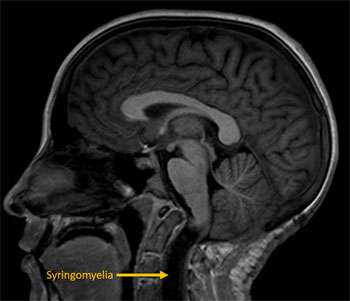

No. In children who do not have any symptoms, we prefer to observe these patients with close clinical follow-up and serial MRI imaging to ensure that the Chiari does not progress. In children who are not symptomatic but show signs of worsening cerebellar herniation, development or progression of syringomyelia or early hydrocephalus, we suggest a strong consideration for surgical treatment. In children that are symptomatic from a Chiari, we recommend surgical treatment. The recommendation for surgery will always be made after careful consideration of the risks of surgery in balance with the risk of not performing surgery.

Possible complications of Chiari can include conditions such as hydrocephalus in which there is excess accumulation of brain and spinal fluid in the head and the development of syringomyelia in which a cavity of brain and spinal fluid develops within the spinal cord. Chiari malformations can also be commonly associated with a tethered spinal cord. This condition results from an abnormal attachment to the bottom of the spinal cord to the bottom of the spinal canal in which the spinal cord is at risk for a “stretch-injury”.

Other tests that we commonly perform may include a sleep study to evaluate for abnormal breathing patterns, a spinal MRI to look for syringomyelia, a thin cut MRI to look for adhesions that are resulting in hydrocephalus or syringomyelia, a CSF flow study to evaluate the flow of brain and spinal fluid at the level of the foramen magnum, and a 3 feet x-ray to evaluate for scoliosis.